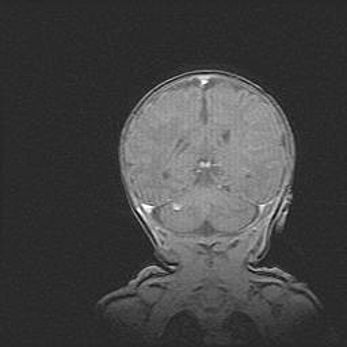

Множественные кисты обоих полушарий головного мозга, наибольшая из них в правой затылочной области. Ассиметричная атрофическая гидроцефалия.

Возраст: 7 месяцев

Вес: 5660 г

Пол: мужской

Окружность головы: 41,5 см

Срок гестации: 28-29 недель

Кисты головного мозга развиваются в результате многоочаговых некрозов вещества мозга и возникают вследствие перенесенной перинатальной инфекции, менингитов, энцефалитов, асфиксии, родовой травмы, расстройств мозгового кровообращения различного генеза. Образованию кист в веществе головного мозга плодов и новорожденных способствуют такие факторы, как высокое содержание в нем воды, недостаточная (или отсутствие) миелинизация и слабая астроглиальная реакция на повреждение.

Кисты могут сочетаться с гидроцефалией и другими поражениями головного мозга.